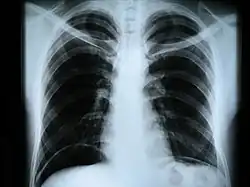

Рентгеногра́фия (от Рентген (фамилия учёного, открывшего этот вид электромагнитных волн) + греч. γράφω, пишу) — исследование внутренней структуры объектов, которые проецируются при помощи рентгеновских лучей на специальную плёнку или бумагу.

Наиболее часто термин относится к медицинскому неинвазивному исследованию, основанному на получении суммарного проекционного изображения анатомических структур организма посредством прохождения через них рентгеновских лучей и регистрации степени ослабления рентгеновского излучения.

- рентгенография грудной клетки — инфекционные, опухолевые и другие заболевания,